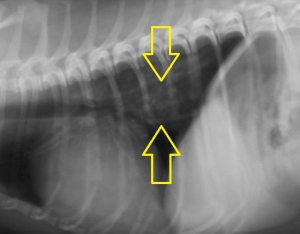

下の写真が食道バリウム造影検査を行って確定診断を行った写真です。同じ部位に造影剤によって明らかになった形のはっきりしない異物が造影されています。

確定診断のための造影レントゲン写真は下のようになりました。バリウムの侵入が少なくやや見にくいですが、四辺形らしい形のはっきりしない食道内異物が確認できます。

【ケース1】の異物よりも造影剤が入らないため見えにくくなっていますが、これは異物が食道粘膜と密着しているということを意味します。その意味は内視鏡検査の際に明らかになります。